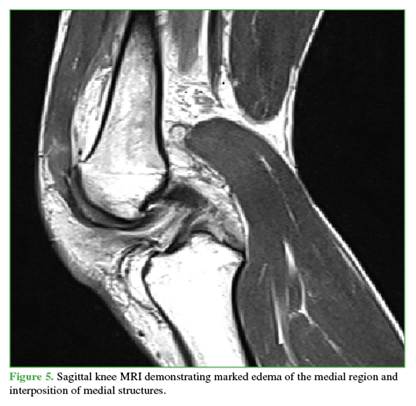

Radiographs showed widening of the medial joint space consistent with medial instability. Further imaging was obtained with magnetic resonance imaging (Figures 4 and 5) to evaluate possible interposed tissues or structures, and with CT angiography (Figure 6) to rule out vascular injury given the time elapsed since trauma. Marked edema was noted in the medial soft tissues, including the capsule and medial structures in the intercondylar region, along with persistent knee subluxation. Vascular compromise was ruled out, with preservation of the femoropopliteal vascular bundle.